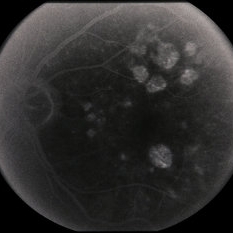

Age Related Macular Degeneration

Age Related Macular Degeneration

Mar 29 2013 by Henry J. Kaplan, MD

Geographic atrophy with small hemorrhages due to subretinal neovascular membrane development.

Condition/keywords: choroidal neovascularization (CNV), geographic atrophy